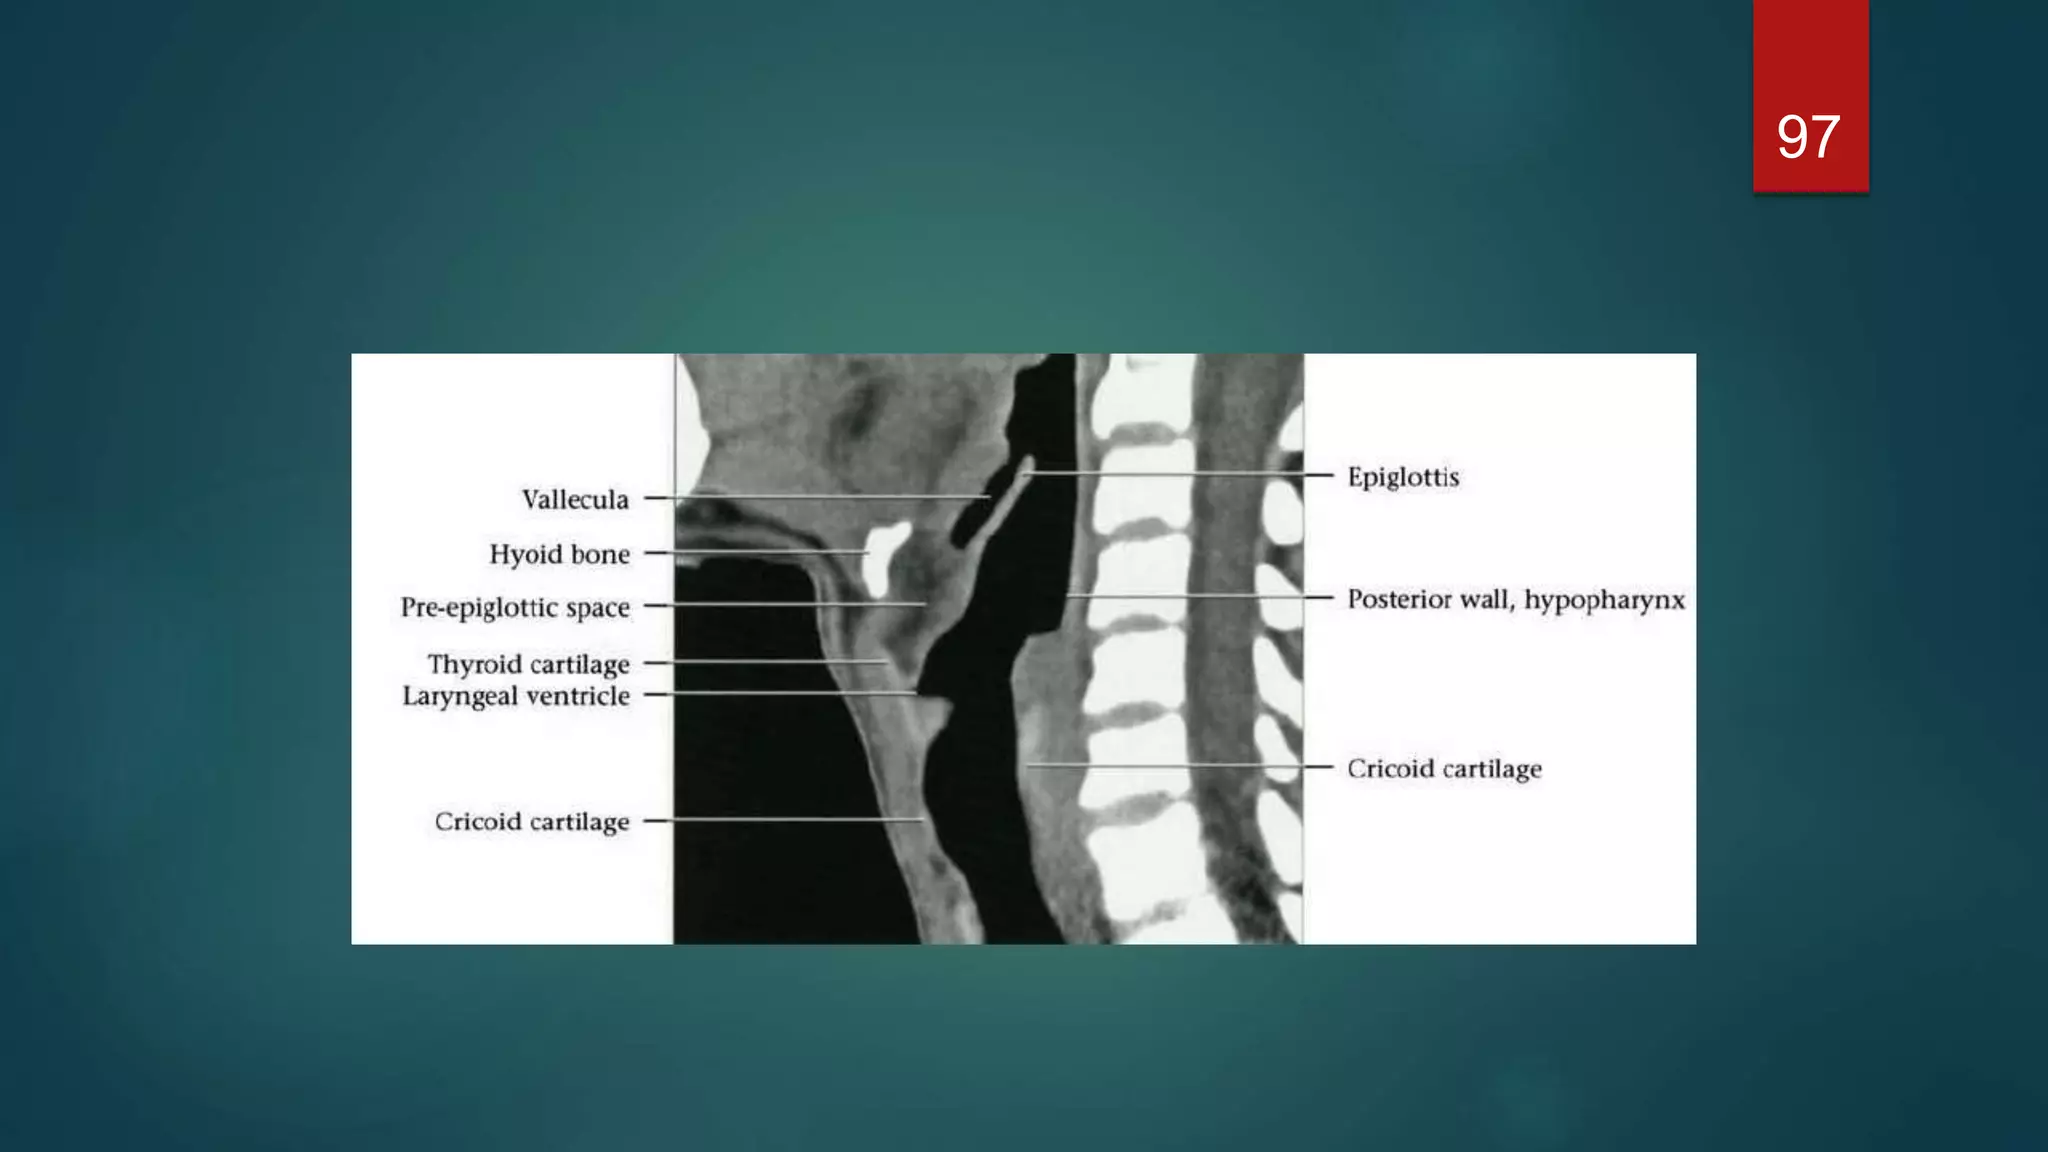

 The epiglottis is a leaf-shaped cartilage whose narrow base

is attached to the inner surface of the thyroid cartilage

 It projects up behind the base of the tongue and directs boluses

laterally into the piriform fossae during deglutition, thus protecting

the larynx.

 Three mucosal folds, the glossoepiglottic folds - namely, a

central and two lateral folds - pass from the anterior surface of

the epiglottis to the base of the tongue. These form paired

recesses between the base of the tongue and the epiglottis

known as the valleculae.

 The cavity of the larynx is divided into three parts by upper and

lower pairs of mucosal folds. The upper pair of folds are the false

cords. The space between the laryngeal entrance and the false

cords is known as the vestibule or the sinus of the larynx.

 The lower pair of folds are the true cords and contain the vocal

ligaments, which are responsible for voice production. The space

between the false and true vocal cords is the laryngeal ventricle.

97